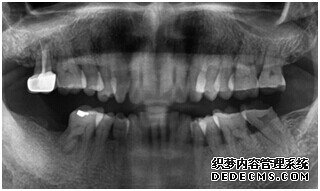

成功植入种植体后的效果图

种植体成功植入后的CT效果图